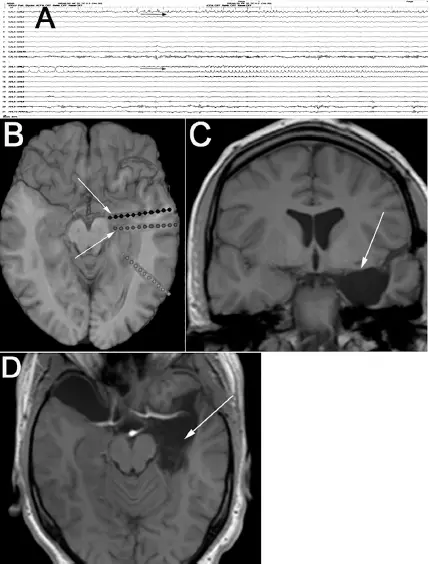

Die Ergebnisse des invasiven Video-EEG-Monitorings belegten die epileptische Genese der Angstzustände. Der Patient wurde im Sinne einer anteromedialen Temporallappenteilresektion behandelt und ist seither ohne Auren und ohne aphasische Anfälle. Er ist postoperativ sehr erleichtert, weil die Angstgefühle ihn stark beeinträchtigt hatten. Die antiepileptische Medikation wird schrittweise reduziert (  Abb. 2.2).

Abb. 2.2).

Abb. 2.2: (A) Angst-Aura mit EEG-Anfallsmuster an den medialen Kontakten der Tiefenelektroden (obere Kontakte CAL = Corpus amygdaloideum links, schwarzer Pfeil; AHL = anteriorer Hippokampus links, grauer Pfeil). (B) Elektrodenlage (das EEG der posterior gelegenen Elektrode – hellgrau – nicht in A gezeigt). (C, D) Postoperatives MRT mit Arachnoidalzyste rechts und Zustand nach Resektion des Corpus amygdaloideum und des Hippokampus links (Pfeile).